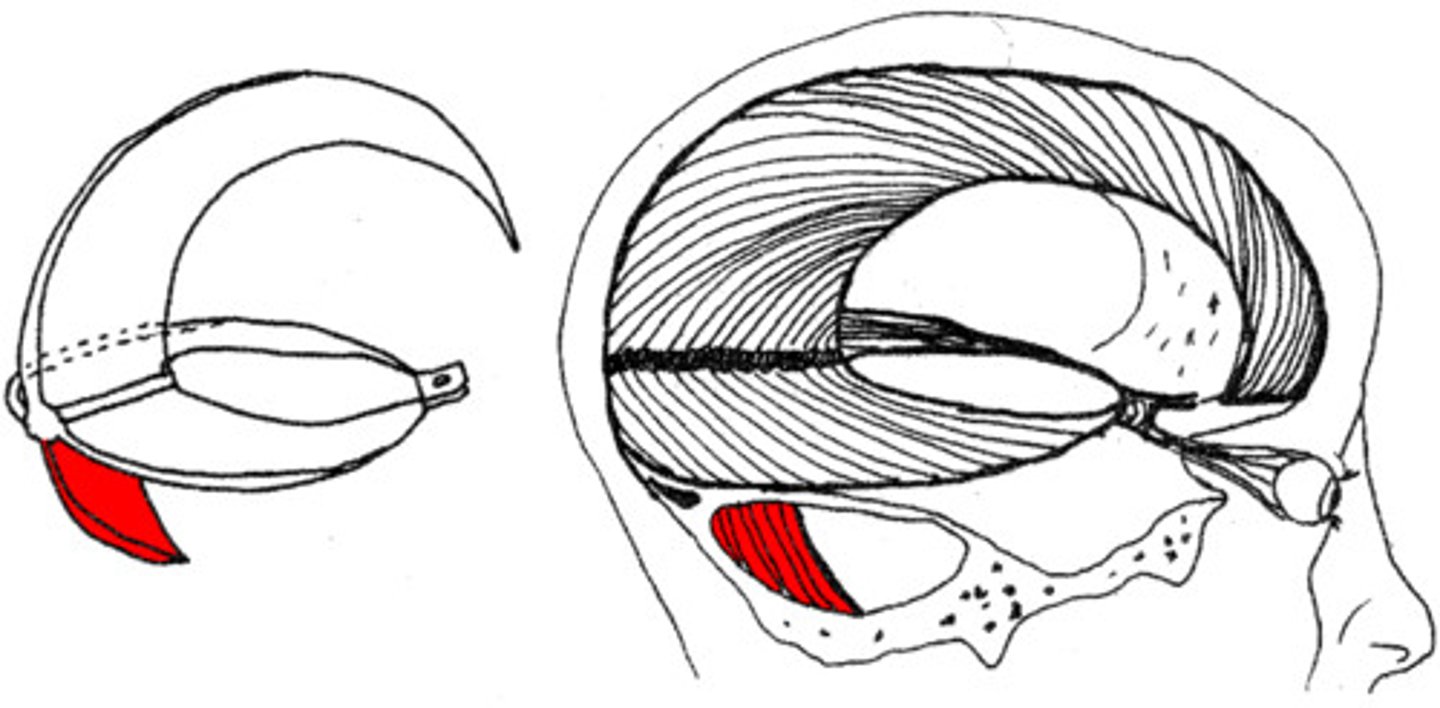

what are dural folds?

folded layers of dura where there is no sinus

falx cerebri

separates the two cerebral hemispheres

tentorium cerebelli

separates cerebrum from cerebellum

falx cerebelli

separates the two hemispheres of the cerebellum